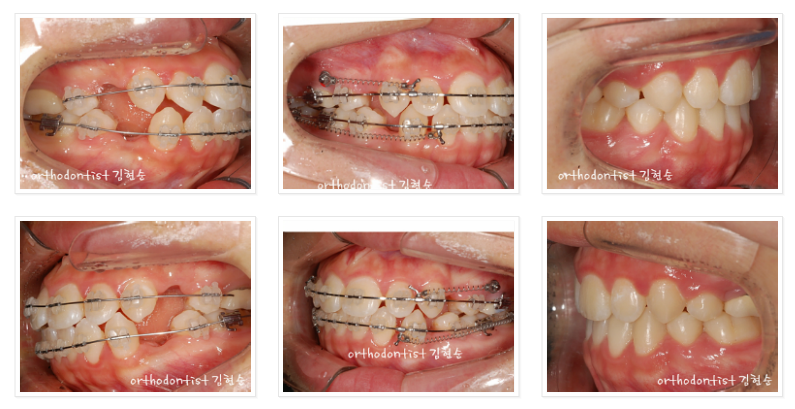

아래 사진들의 가운데 열에

보이는 미니스크류를

어금니 윗쪽에

설치했습니다.

위 아래 사진의

좌측 사진들은

발치 후 세라믹 교정 초기이고

가운데 사진들은은

세라믹 교정 시행 6개월 후인

미니스크류 설치 후,

그리고 우측 사진들은

세라믹 교정 완료 단계의

사진들입니다.

참고로

가운데 사진의 미니스크류는

교정 시작 후 약 6개월 후,

즉 앞니를 끌어당길 준비가 완료될 때

마취 후 설치합니다.